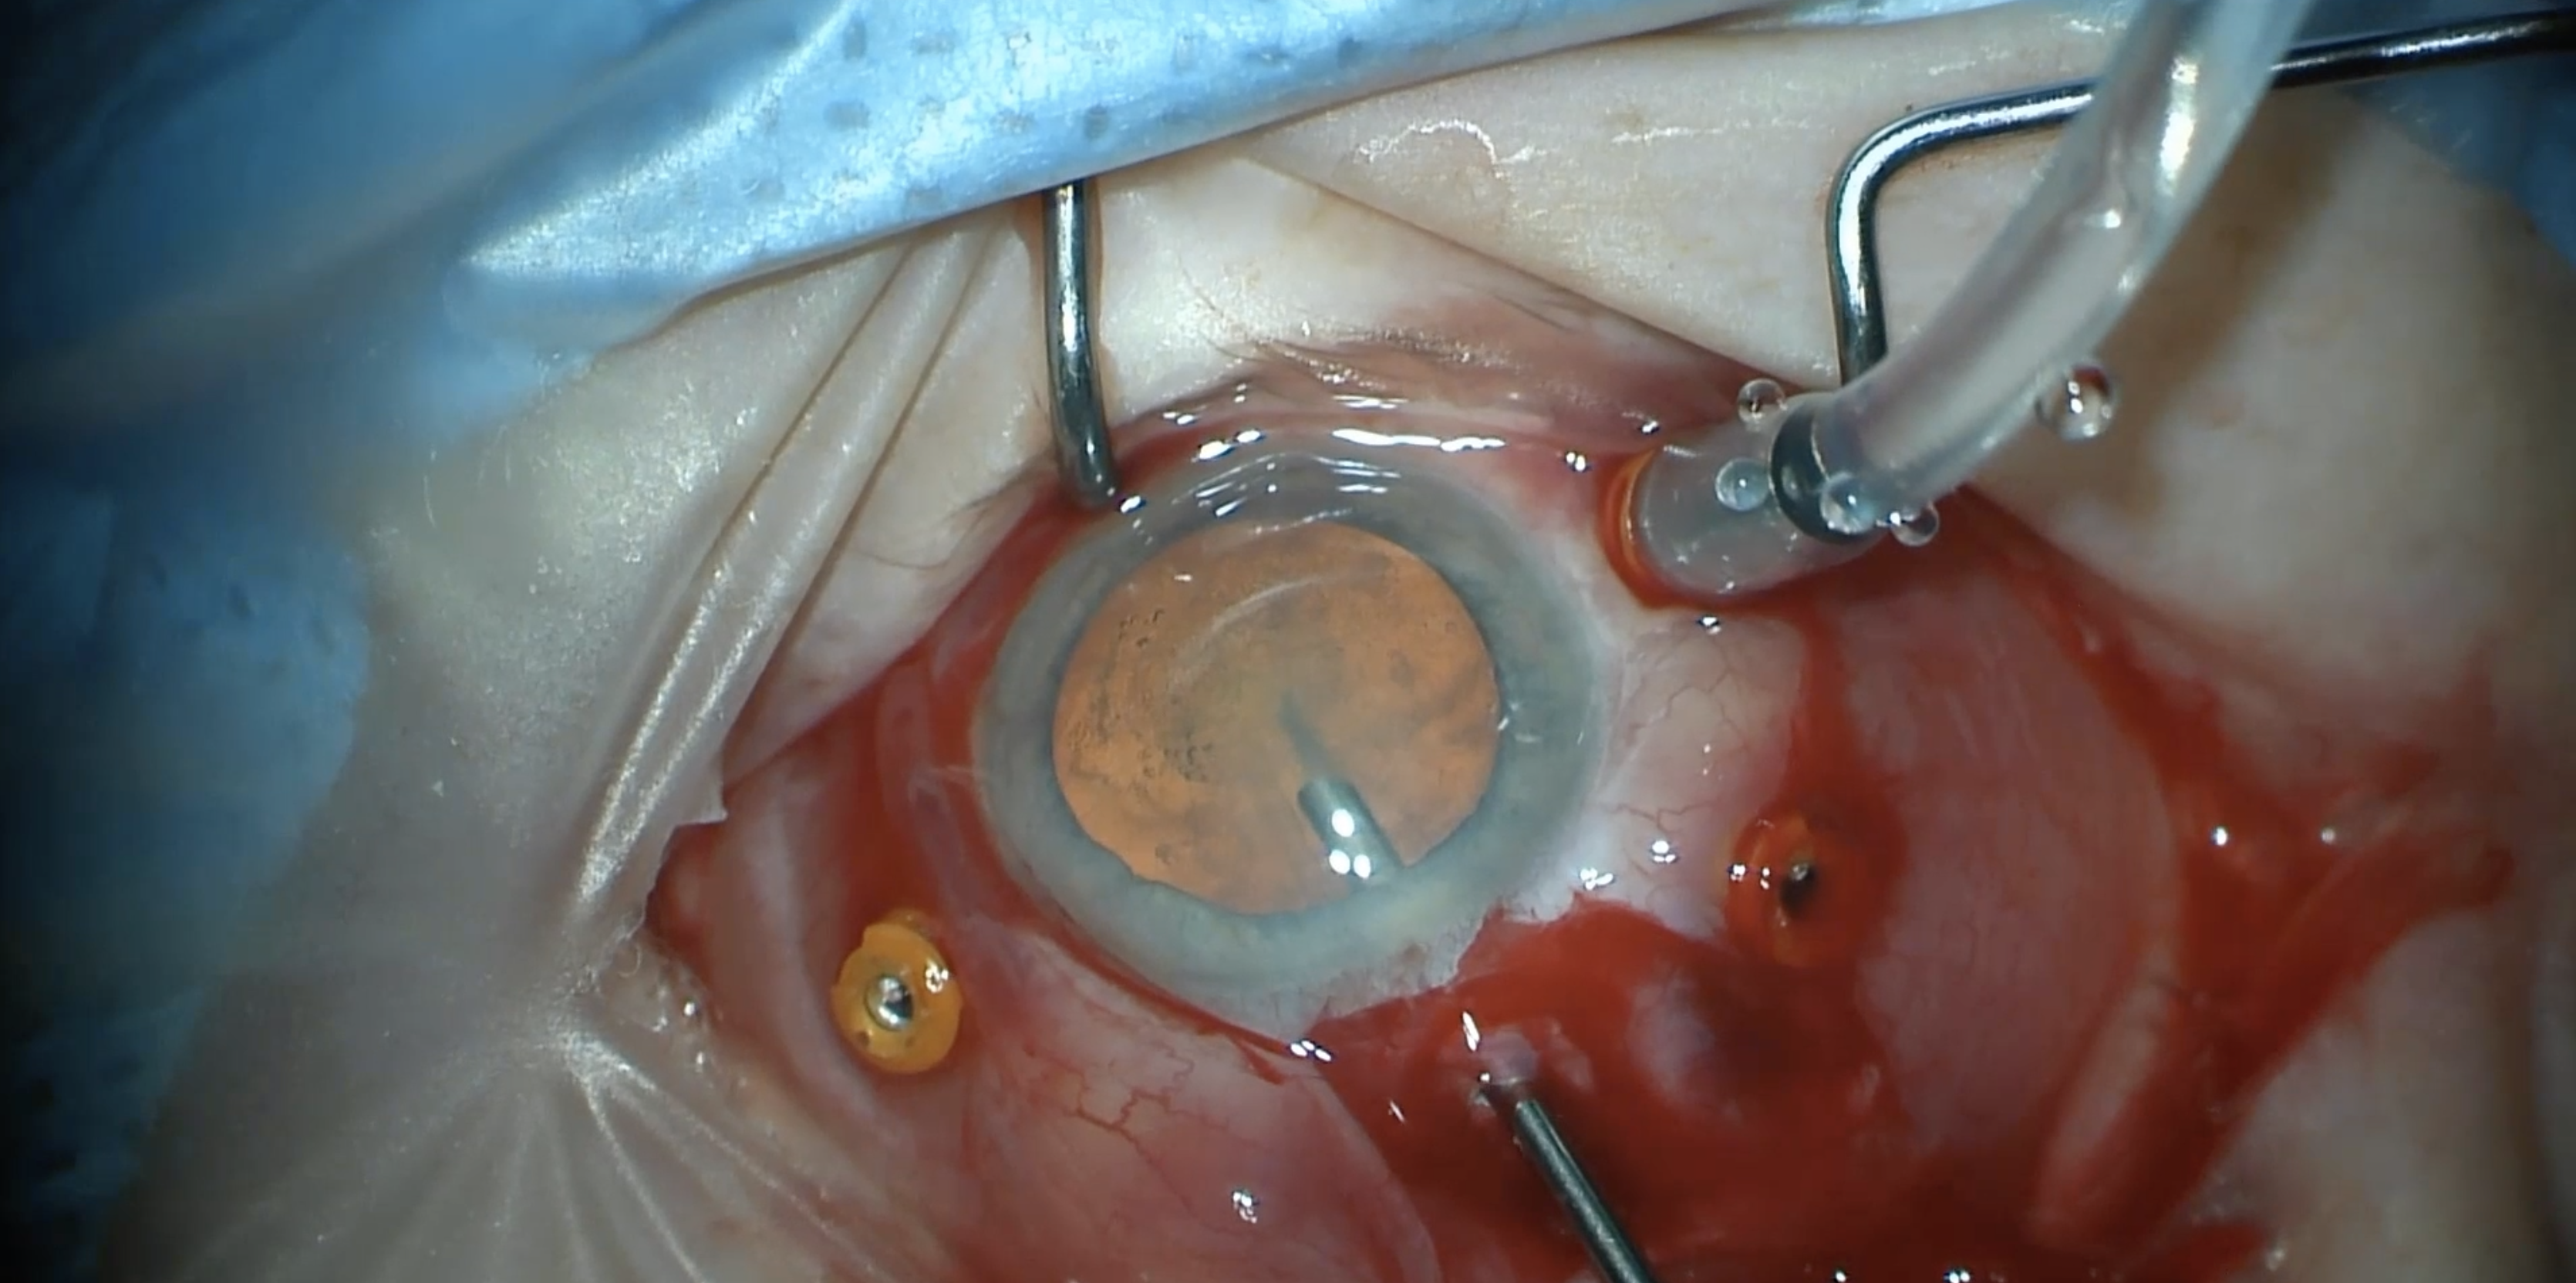

Retinal Detachment Associated with Retinal Dialysis A soccer player presented to the Bascom Palmer Emergency Department after failing a driver’s test. Past medical history was unremarkable. Exam was notable for visual acuity of 20/20 in the right eye and 20/300 in the left eye. Intraocular pressu…